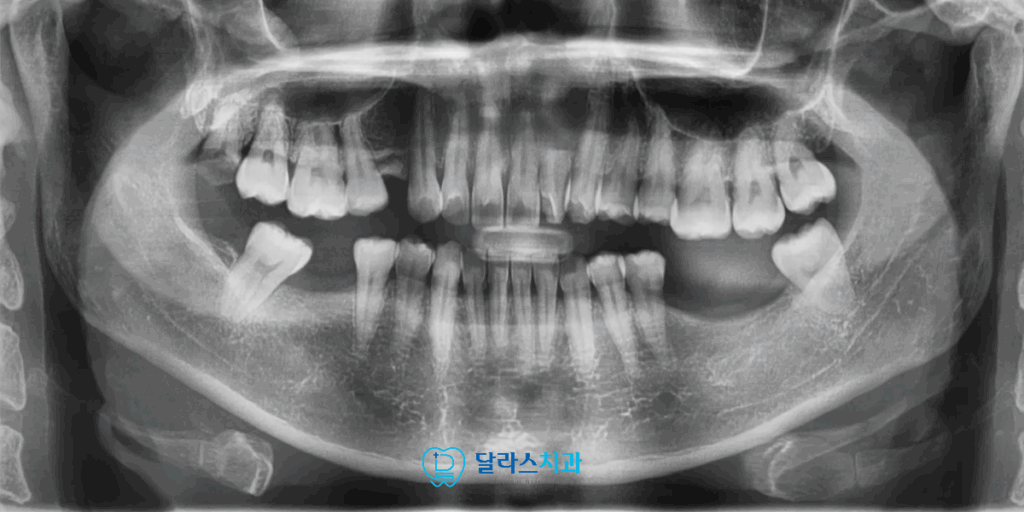

이번에 노원역치과에 내원하신 40대 여성 환자 분께서는

상실된 어금니 부위와 상실 부위로 정출된 대합치,

쓰러진 인접 치아로 인해 여러 문제가 복합적으로 나타나고 있는 상태였습니다.

측면에서 바라보는 X-ray를 촬영하여 골격적인 부분도 함께 확인해보았습니다.

구강 내 배열을 보면 위 아래 악궁이 V자 형태로 돌출감이 있는 상태였습니다.

씹는 부분에 패인 홈들을 따라서 까맣게 선 또는 점들이 보이는데 이것들은 모두 충치입니다.

충치가 구강 내 전반에 걸쳐서 발생해 있어 충치 치료를 통해서 해결해야하는 상황이었습니다.

측면과 정면상태를 보면 상실된 어금니 부위 인접 치아들이 쓰러져있고

정출되어 있는 것을 구강내 검진을 통해서 확인할 수 있습니다.